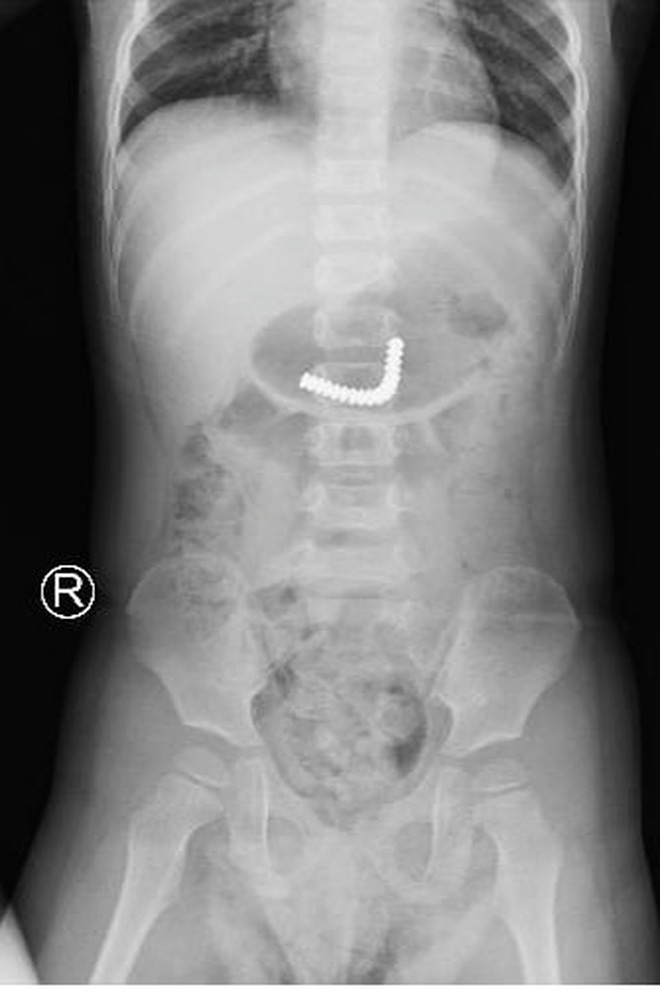

22/12/2020 22:30TP.HCM: Cầm máy massage mắt của mẹ chơi, bé trai 3 tuổi nuốt luôn 18 viên nam châm vào bụng

Ngày 22/12, BV Nhi đồng Thành phố cho biết vừa tiến hành phẫu thuật thành công cho trường hợp bé trai 3 tuổi sau khi nuốt nam châm vào bụng.

Cụ thể trước khi nhập viện, trong lúc cầm máy massage mắt của mẹ chơi, bé đã nuốt hết số bi nam châm vào bụng. Mẹ bé phát hiện liền tá hỏa đưa con đi nhập viện, thời điểm này bé không đau bụng, không ói nhưng vô cùng hoảng loạn.

Chụp phim kiểm tra, các bác sĩ thấy dị vật trong dạ dày. Bệnh nhi được đưa đi nội soi tiêu hóa khẩn thì thấy dị vật đã xuống ruột non. Các bác sĩ tua trực quyết định khẩn trương mổ nội soi thám sát, lấy dị vật là 18 viên nam châm dính kết chùm lại ra ngoài an toàn.

Sau mổ, bé trai hồi phục tốt và dự kiến xuất viện sau vài ngày tới. Theo BS Đỗ Huy Trọng Hiếu, khoa Ngoại Tổng hợp cho biết trẻ nhỏ thường hay khám phá thế giới xung quanh bằng việc cho mọi thứ vào miệng nên hay xảy ra trường hợp nuốt dị vật, đặc biệt là bi sắt, nam châm vào bụng.